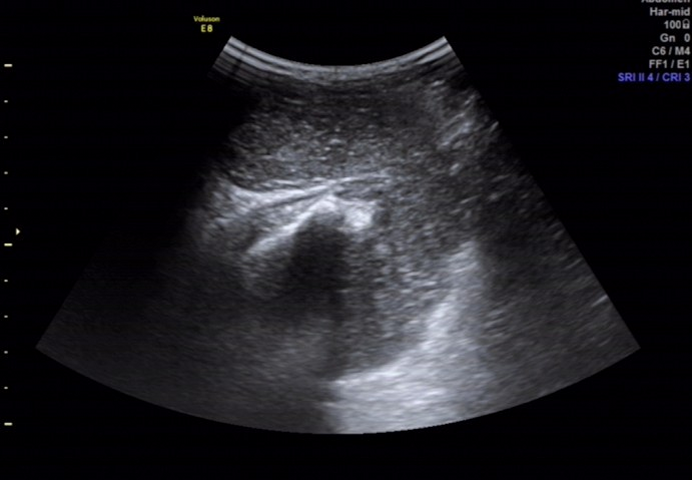

超声所见

骶尾部皮下软组织层内探及一范围约 145×98×107mm 的低回声包块,围绕骶骨生长,部分向盆腔内生长,与周围其他组织分界清楚,内部回声欠均匀, CDFI:内见多个条状血流信号, PW 检测:呈动脉频谱, RI:0.72 。

图 2 用凸阵探头经骶尾部扫查见包块围绕骶骨生长,并与骶骨分界不清